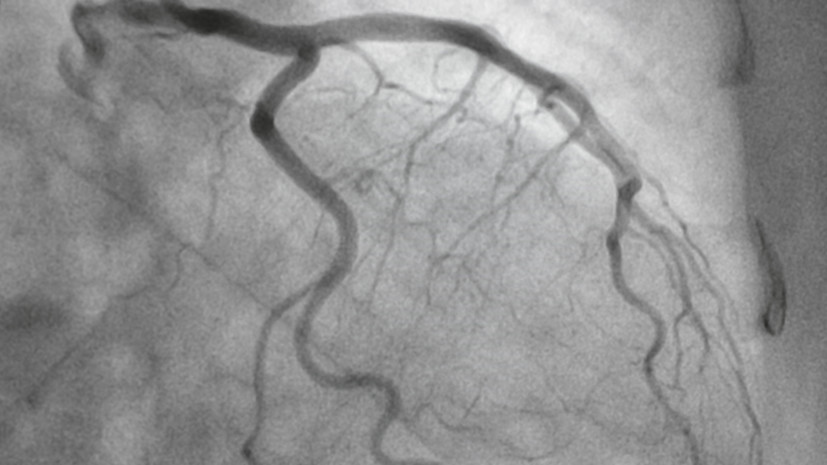

Врач Платонова: ангиографию стоит делать только после перенесённого инфаркта

По её словам, ангиография высокоинформативна, но требует строгих показаний и учёта накопленной дозы.